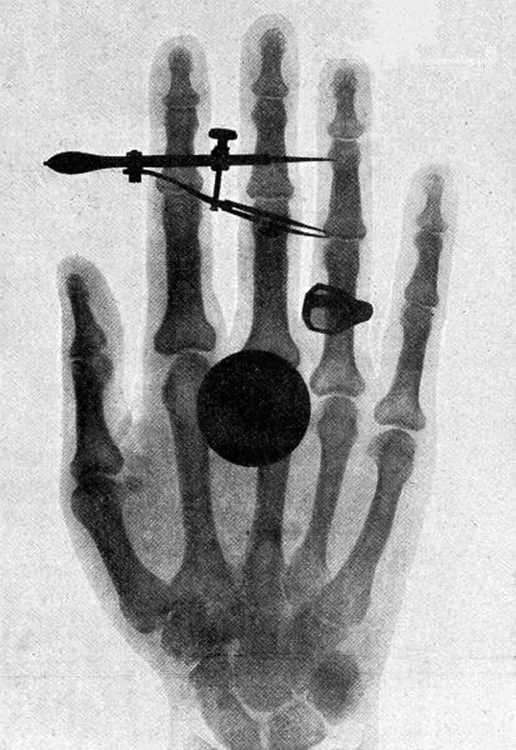

An x-ray image of Bertha Röentgen’s hand is shown with a dark circular spot superimposed on the fingers.

Figure 29.12 One of the first x-ray images, taken by Röentgen himself. The hand belongs to Bertha Röentgen, his wife. (credit: Wilhelm Conrad Röntgen, via Wikimedia Commons)

High photon energy also enables γγ size 12{γ} {} rays to penetrate materials, since a collision with a single atom or molecule is unlikely to absorb all the γγ size 12{γ} {} ray’s energy. This can make γγ size 12{γ} {} rays useful as a probe, and they are sometimes used in medical imaging. x rays, as you can see in Figure 29.11, overlap with the low-frequency end of the γγ size 12{γ} {} ray range. Since x rays have energies of keV and up, individual x-ray photons also can produce large amounts of ionization. At lower photon energies, x rays are not as penetrating as γγ size 12{γ} {} rays and are slightly less hazardous. X rays are ideal for medical imaging, their most common use, and a fact that was recognized immediately upon their discovery in 1895 by the German physicist W. C. Roentgen (1845–1923). (See Figure 29.12.) Within one year of their discovery, x rays (for a time called Roentgen rays) were used for medical diagnostics. Roentgen received the 1901 Nobel Prize for the discovery of x rays.